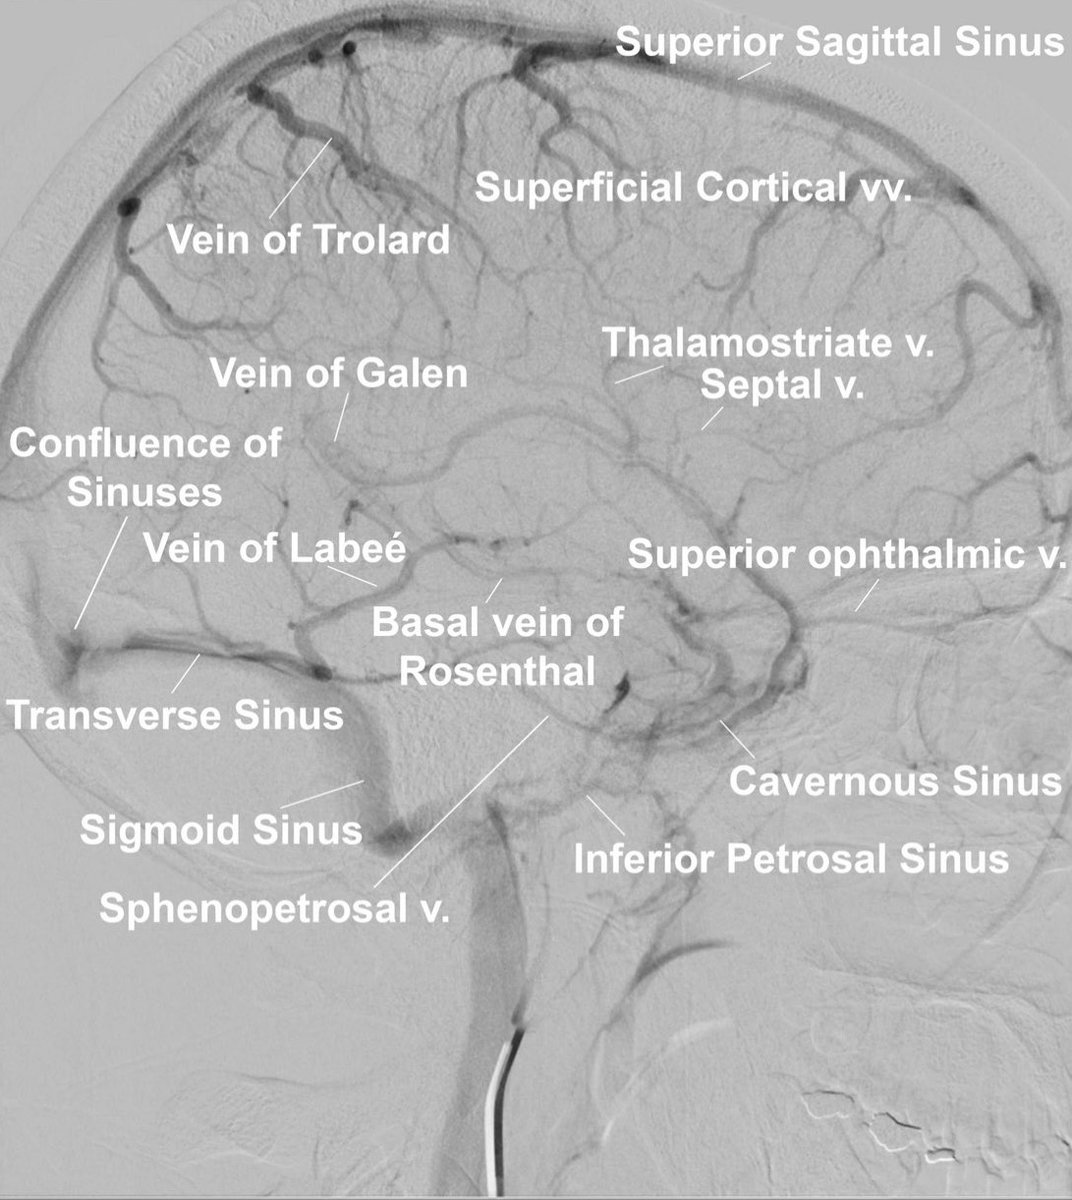

⭕️MCA occlusions / 🧠 infarct patterns Maybe time for this👇again Andrew Micieli? #MedTwitter #MedStudentTwitter #MedEd #FOAMed #neurotwitter #Neurology #stroke #Neurosurgery #EndNeurophobia #FOAMrad #NeuroRad #neuroradiology #radiology #radres #RadEd #FOAMncc #MRI